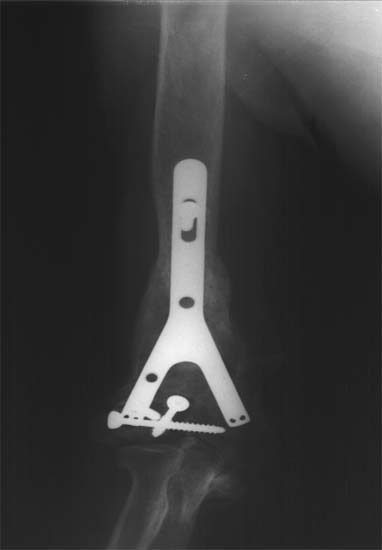

股骨远端骨折术后10年,4次手术均失败。经带锁髓内钉内 固定、植骨,骨生长因子和骨髓细胞注射,成功治愈